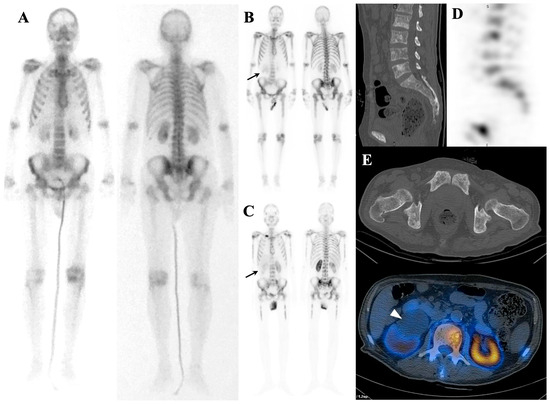

7.3. Distinguishing Metabolic Superscan from Metastatic Superscan